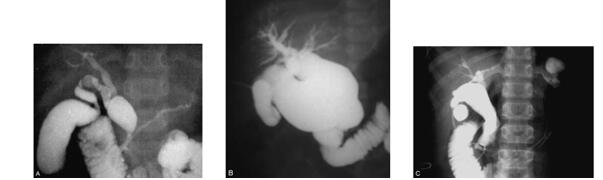

图7:CT 所示的先天性胆管扩张症的肝内胆管扩张

(1)平面CT所示的先天性胆管扩张症的肝内胆管扩张

(2)CT三维成像所示先天性胆管扩张症的肝内胆管扩张。

8、核磁共振及核磁共振胰胆管成像技术(MRCP)

是90年代才成熟应用到临床的一种高新无创成像技术。利用核磁共振的特殊呈像技术获得清晰的胰胆管呈像效果,甚至可明确地判断出是否合并胰胆合流异常。近年大量临床研究表明,单纯的胆管扩张症的 诊断远不能适应正确指导手术。(图8)

图8:先天性胆管扩张症的MRI, MRCP检查

(1)(2)平面MRI所示的先天性胆管扩张症肝内胆管的扩张

(3) MRCP检查所示的先天性胆管扩张症合并胰胆管合流异常。